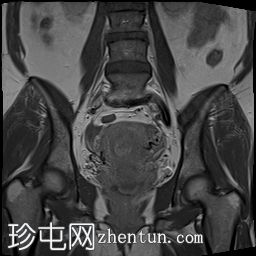

冠状位

T2加权像

可见子宫外腹腔内妊娠囊,内含胎儿组织。

该妊娠囊向后推移子宫,并与剖宫产瘢痕凹陷处紧密相连。

该妊娠囊与相关肠袢无法分离。可见其与性腺血管密不可分,且性腺血管明显突出。

胎盘位于妊娠囊后方,紧贴子宫前壁。

沿妊娠囊下缘可见一处异质性局灶性积液,最大轴向尺寸约为 8.4 × 5.5 cm,T1 加权像呈异质性高信号,T2 加权像呈异质性中等信号,T1 脂肪抑制序列未见信号下降,提示为血液成分。该积液压迫膀胱。

右侧卵巢未见实性或囊性肿块。

子宫体积增大,后倾,子宫内膜厚度约 1 cm,子宫下段前壁可见局灶性变薄(既往子宫瘢痕)。子宫连接区完整,未见肌层肿块。可见子宫内膜腔边缘有血性分泌物。